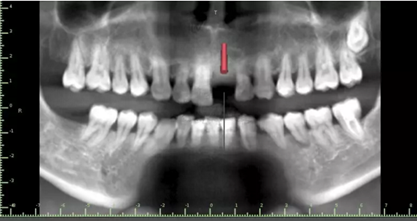

1.術(shù)前CT

2.術(shù)前植體設(shè)計(jì)

3.術(shù)前導(dǎo)板設(shè)計(jì)